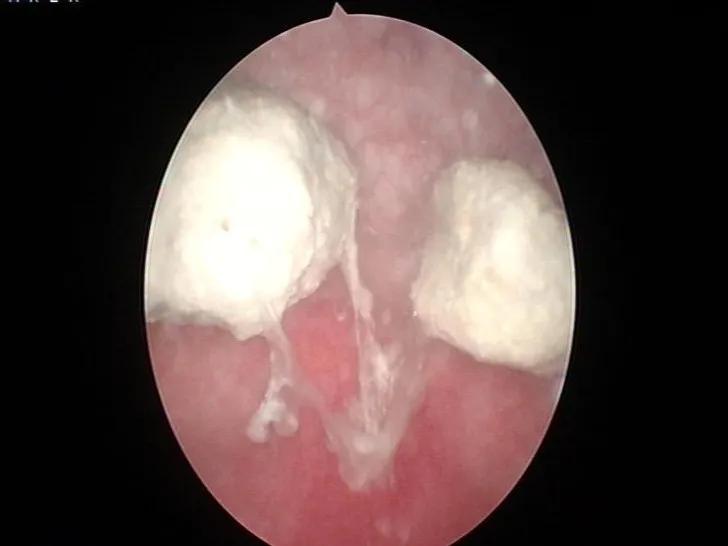

外一科主任靳永池认为此为罕见病例,随即安排主治医师何晓北为患者进行膀胱镜检查,膀胱镜下两枚奇异的结石无所遁形,灰白色,一大一小,固定于膀胱顶部,与膀胱壁间有蓝绿色金属丝相连。妇产科副主任医师李丽芬和主治医师周秀军一致认为,此为“爱母环”移位进入膀胱并形成结石。